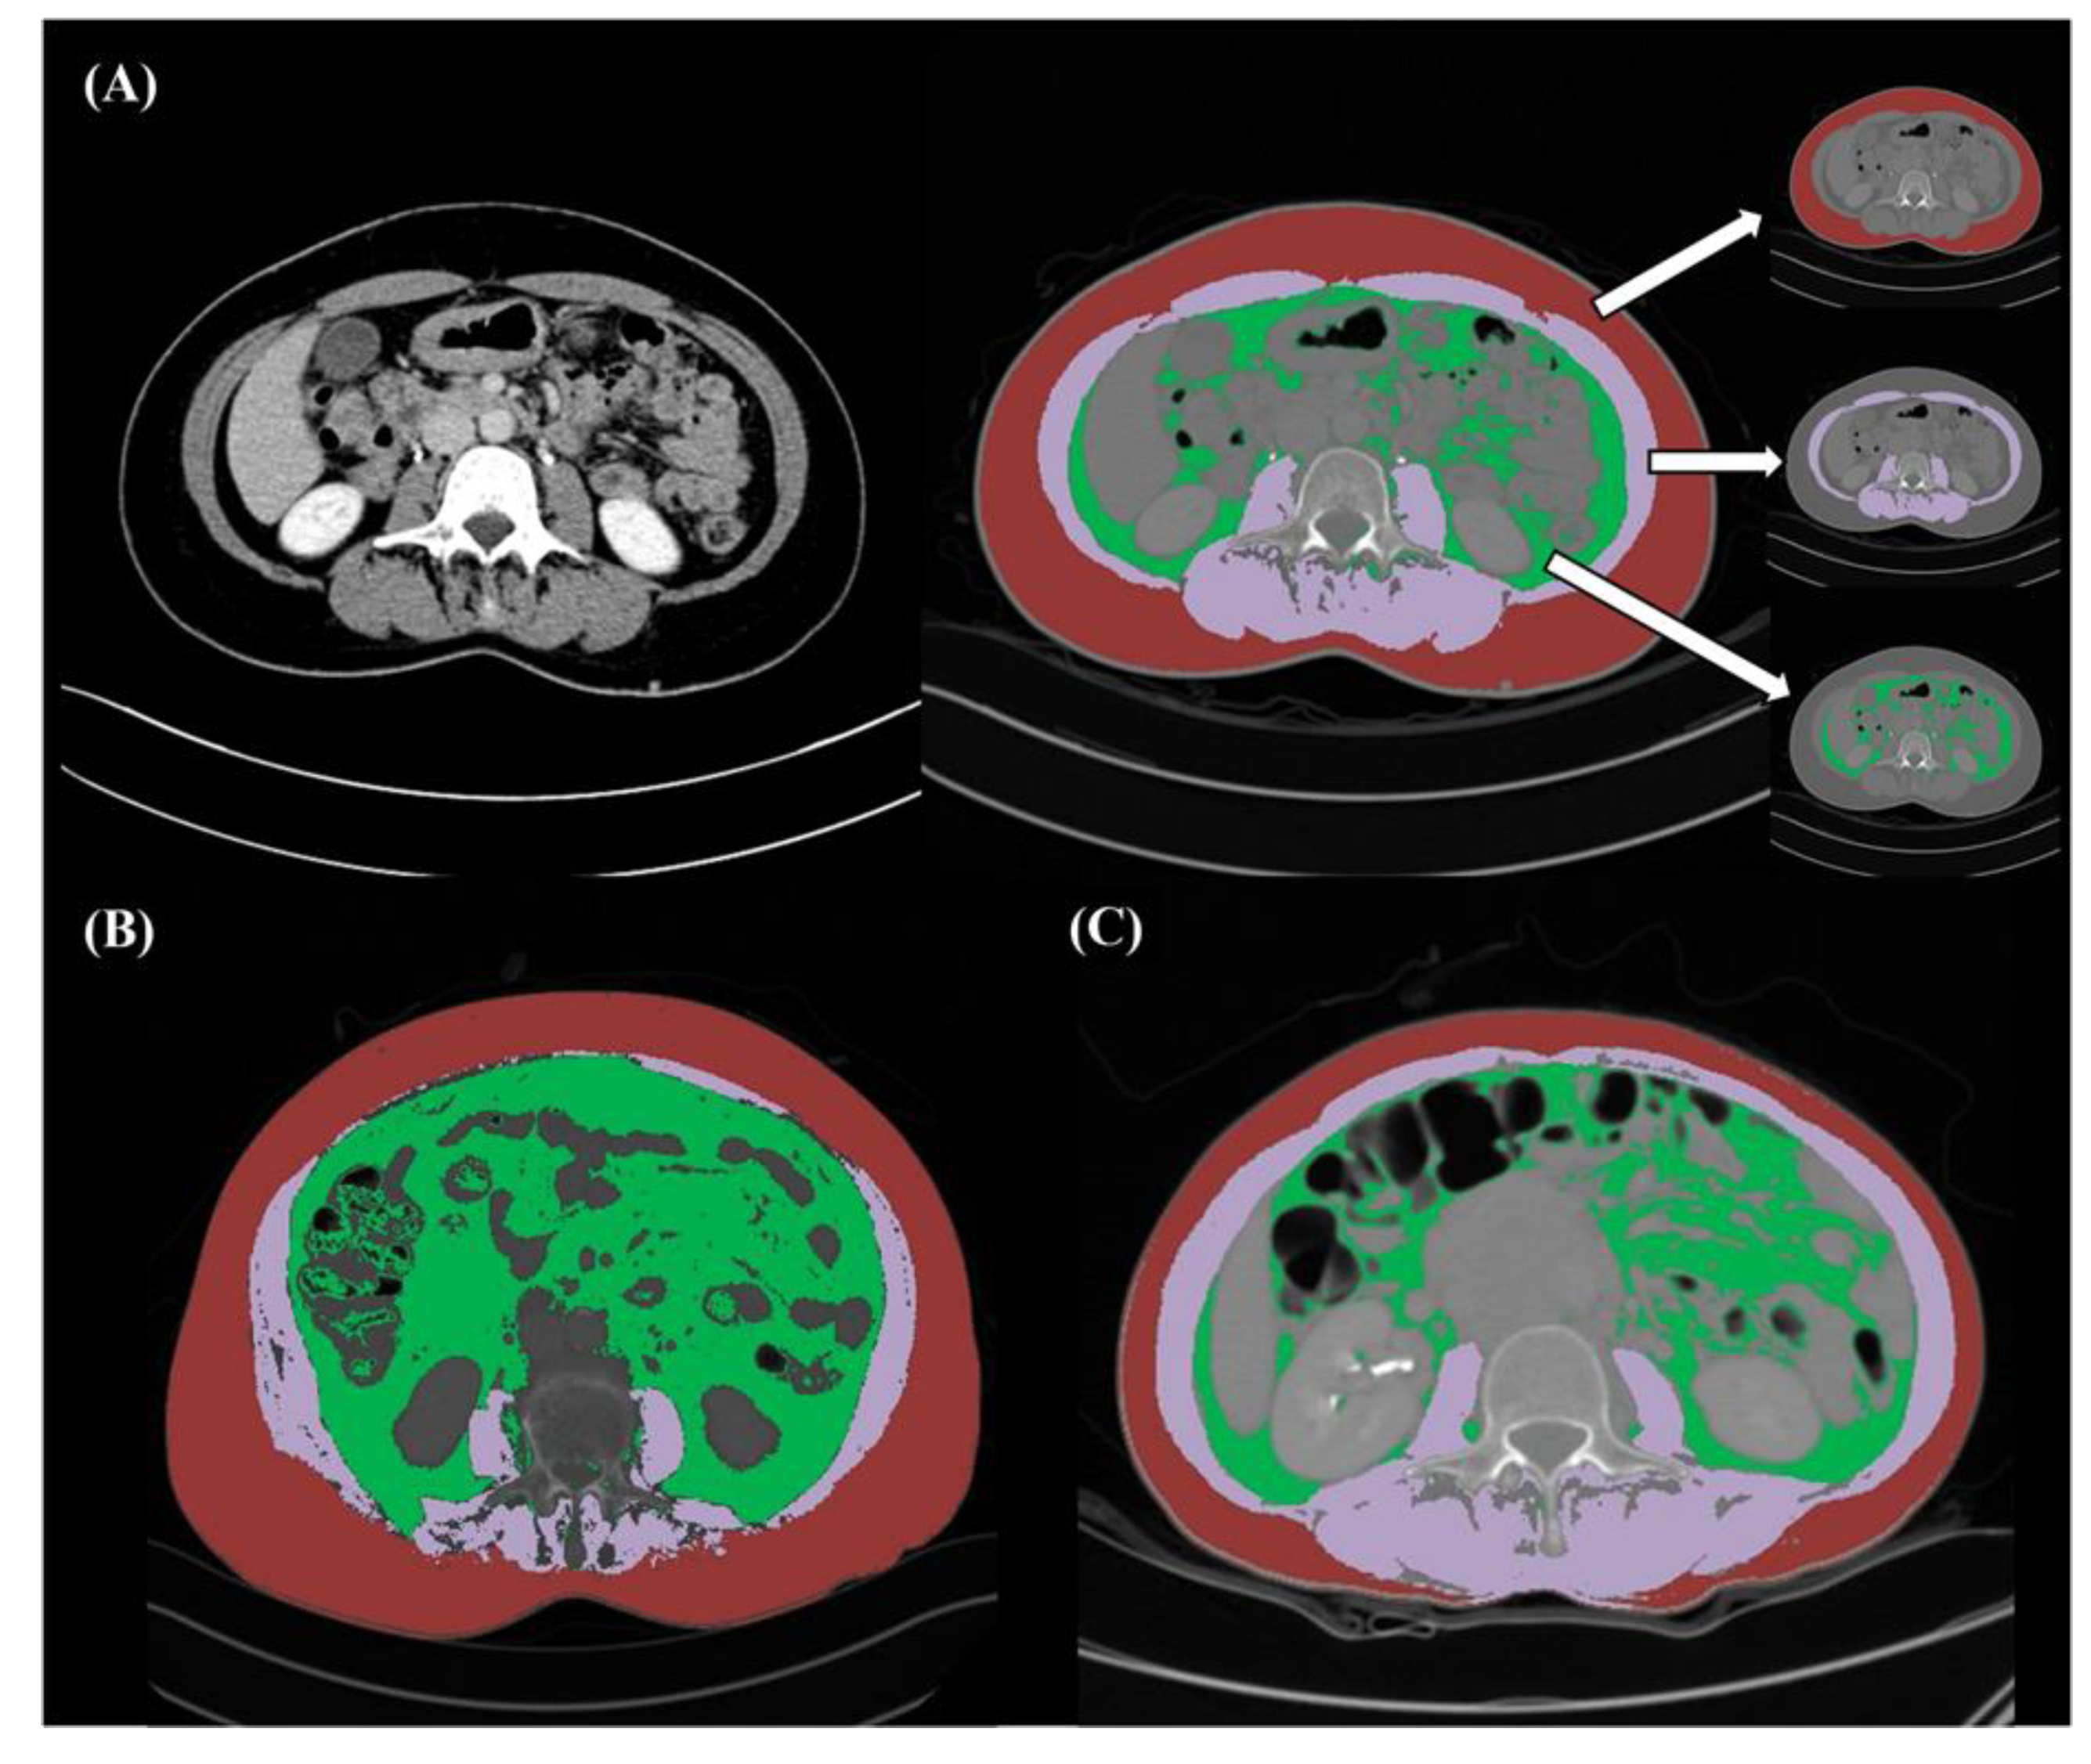

4.2. CT Image Analysis and Definition of Sarcopenia